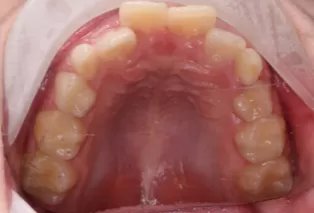

Photos intra-orales